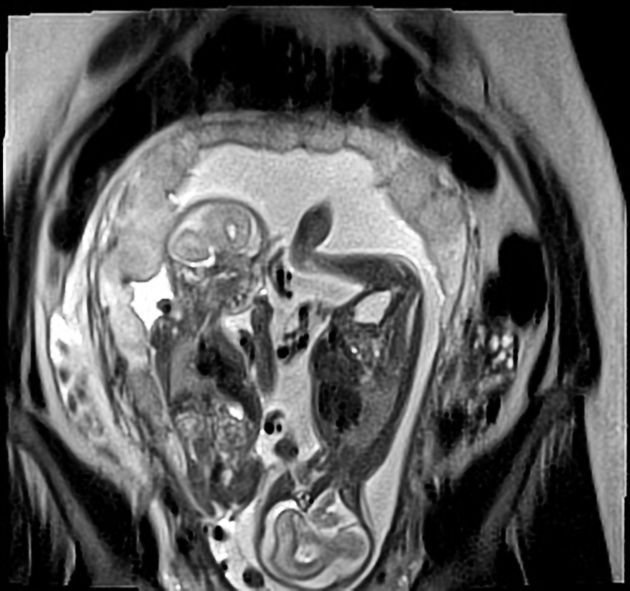

Twin to twin transfusion syndrome (TTTS) is a potential complication that can occur in a monochorionic (either MCDA or MCMA) twin pregnancy.

TTTS results from unbalanced vascular (arteriovenous and arterioarterial) anastomoses in the placenta - that is, placental circulation is directed predominantly towards one twin and away from the other.

The resultant hypovolaemia and hypoperfusion in one twin and hypervolaemia and hypertension in the other create a cascade of hormonal changes including the renin-angiotensin system. This in turn leads to chronic tubulopathy and oliguria in the hypovolaemic (donor) twin with consequent oligohydramnios, and polyuria and consequent polyhydramnios in the hypervolaemic (recipient) twin.

Monochorionicity is a prerequisite at any stage of gestation.

Growth discordance is often but not invariably present, and does not contribute to diagnostic criteria.

Second and third trimesters

Features that may be noted individually in each twin include:

recipient twin

polyhydramnios (deepest vertical pocket (DVP) >8 cm)

donor twin

oligohydramnios (DVP <2 cm), which may result in the twin appearing pinned to the side of the gestational sac: “stuck twin”

small or non-visualised urinary bladder